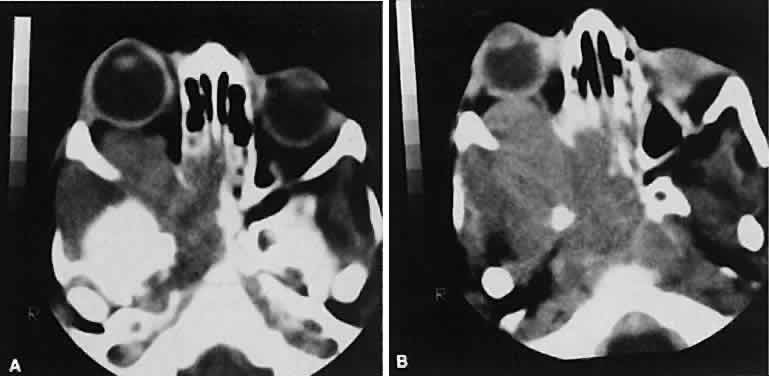

Fig. 7. Graves' orbitopathy with two variations. Axial (A) and coronal (B) views show symmetric fusiform enlargement of the extraocular muscles with tapered muscle insertions. Note the predominant enlargement of the inferior, medial, and superior rectus muscles with lesser involvement of the lateral rectus muscle, a frequent pattern of enlargement in Graves' orbitopathy. Axial (C) and coronal (D) views of Graves' orbitopathy with expansion of retrobulbar ground substance and relative sparing of the extraocular muscles.

CT evidence of Graves' orbitopathy tends to be bilateral. Approximately 86% of patients with unilateral clinical findings have bilateral CT findings in our experience, which is consistent with the experience of others.42

Morphologically, the EOM belly is enlarged, with a gradual tapering toward and sparing of the tendinous portion of the muscle. Tendon involvement is a typical feature of orbital myositis. Tendon involvement helps to differentiate this lesion from Graves' orbitopathy, although Rootman and Nugent43 have noted a rare patient with Graves' orbitopathy with this finding.

The muscle belly has a smooth contour with no edema of the adjacent orbital fat. We recently evaluated a patient with a referral diagnosis of Graves' orbitopathy. The patient was euthyroid but had severe orbital congestion typical of advanced Graves' orbitopathy. Imaging showed “dirty” orbital fat and lateral rectus muscle morphology that seemed atypical (Fig. 8). Biopsy specimen results showed a low-grade lymphoma. Hypertrophy of the medial rectus muscle can cause the medial wall to bow in toward the ethmoidal sinus from the chronic effects of pressure on the bone. The hypertrophied muscles also can give rise to a compressive optic neuropathy in the orbital apex as the enlarged muscles take their origin from the anulus of Zinn. Axial views of the apex show an apparent mass if the inferior rectus muscle is enlarged. It is imperative that additional views, sagittal or preferably coronal, be obtained to show the true nature of this apparent mass. Intracranial fat prolapse, seen by CT, may be another sign of optic neuropathy.44 An optic neuropathy also can be seen with relatively normal-sized EOM. An expanded fat compartment with optic nerve stretch has been associated with an optic neuropathy.45,46